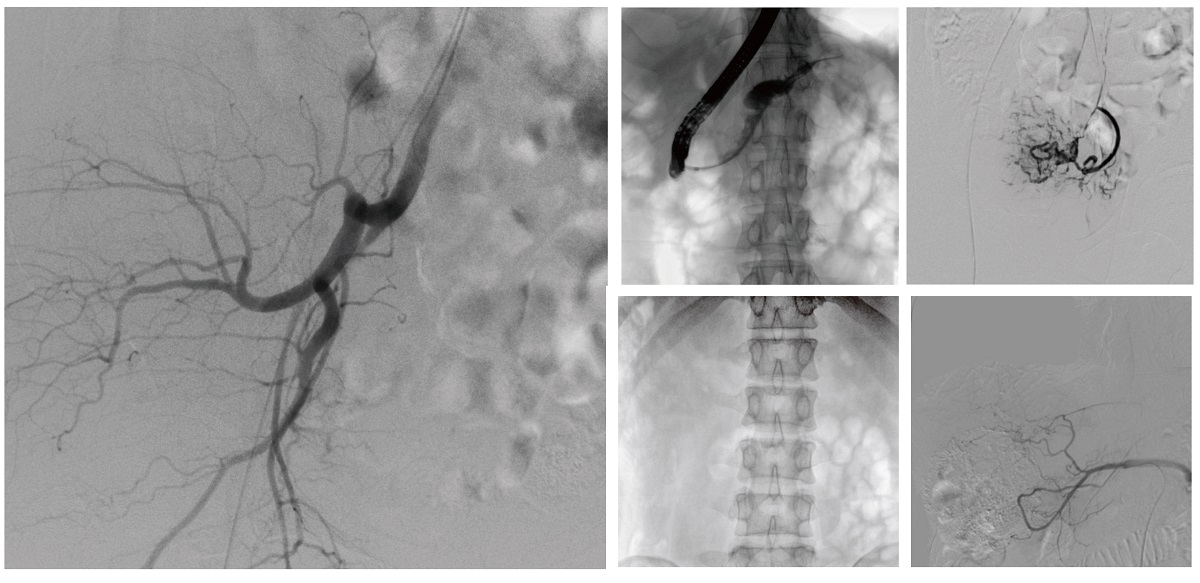

醫(yī)院引進的普愛醫(yī)療移動式平板介入中C,其高清成像能力覆蓋骨科、介入科、泌尿外科、婦產科等多科室,能夠滿足介入微創(chuàng)手術的多樣化需求。

設備的移動式設計,無需對現有手術室進行改造,適合高負荷手術量或應急情況下的靈活部署。如在急診介入手術中,該設備能迅速響應需求,為醫(yī)生提供實時影像支持,提升搶救效率。